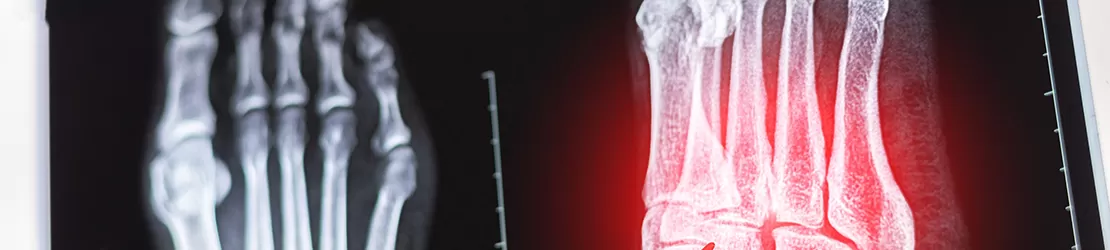

Medic care analizeaza o radiografie a piciorului si degetelor pentru a evalua structurile osoase si posibile afectiuni

Diagnosticare

• radiografia: poate fi normală la debut (stadiul 0); în stadiile avansate, evidențiază:

• fracturi;

• dislocări;

• eroziuni;

• colaps osos.